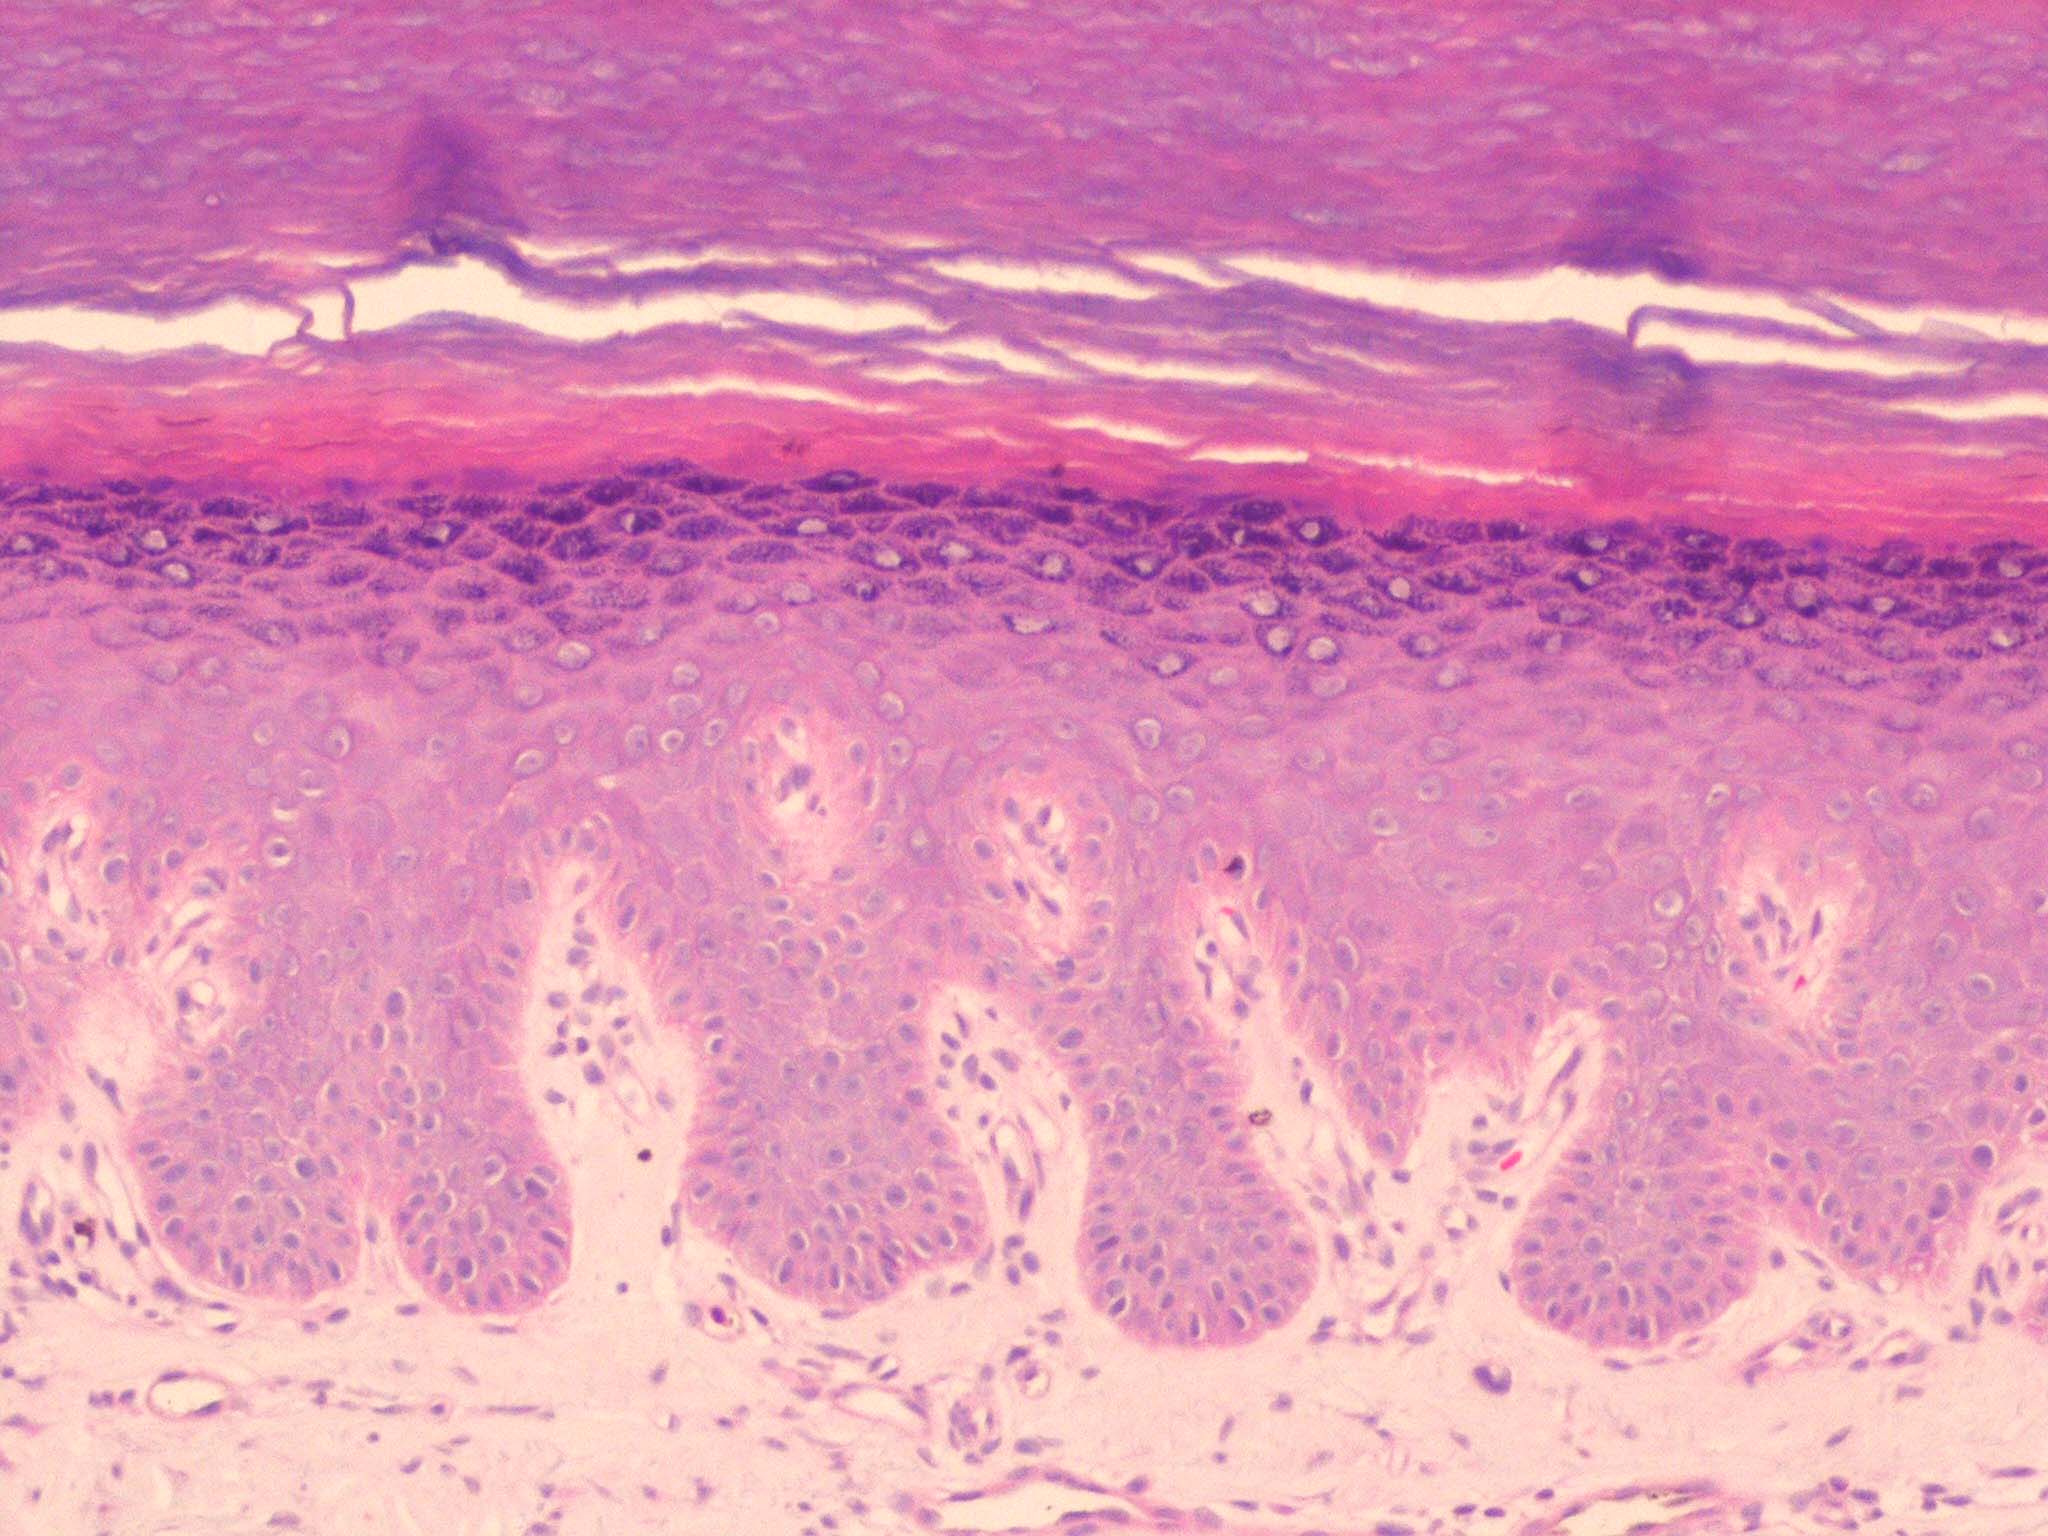

In keratosis palmaris et plantaris of the Unna-Thost type and the Meleda type, as well as in the Papillon-Lefevre syndrome, the histologic picture is nonspecific, consisting of considerable hyperkeratosis, hypergranulosis, acanthosis, and a sparse inflammatory infiltrate of lymphocytes in the upper dermis .

In epidermolytic keratosis palmaris et plantaris, the histologic picture is identical with that seen in epidermolytic hyperkeratosis. Many cells in the middle and upper stratum malpighii appear vacuolated, and scattered cavities are present as a result of ruptured cell walls. Keratohyaline granules are numerous and large .